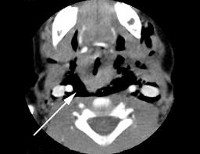

Диагностикой наружных травм глотки занимаются преимущественно травматологи. При этом важное значение имеют осмотр раны и раневого канала, определение характера ранения (проникающее или непроникающее), объективная оценка степени тяжести состояния пострадавшего. В диагностике наружных травм глотки для определения их характера и степени повреждений могут применяться рентгенологические исследования и компьютерная томография глотки, МРТ и УЗИ мягких тканей шеи, рентгенография позвоночника, КТ околоносовых пазух и КТ черепа. В неотложных случаях диагностика травмы глотки производится интраоперационно.